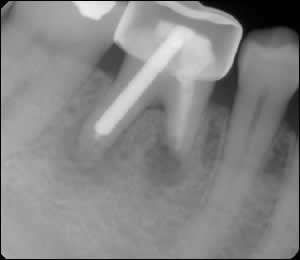

Fig 1: A diseased tooth proved to be hopeless.